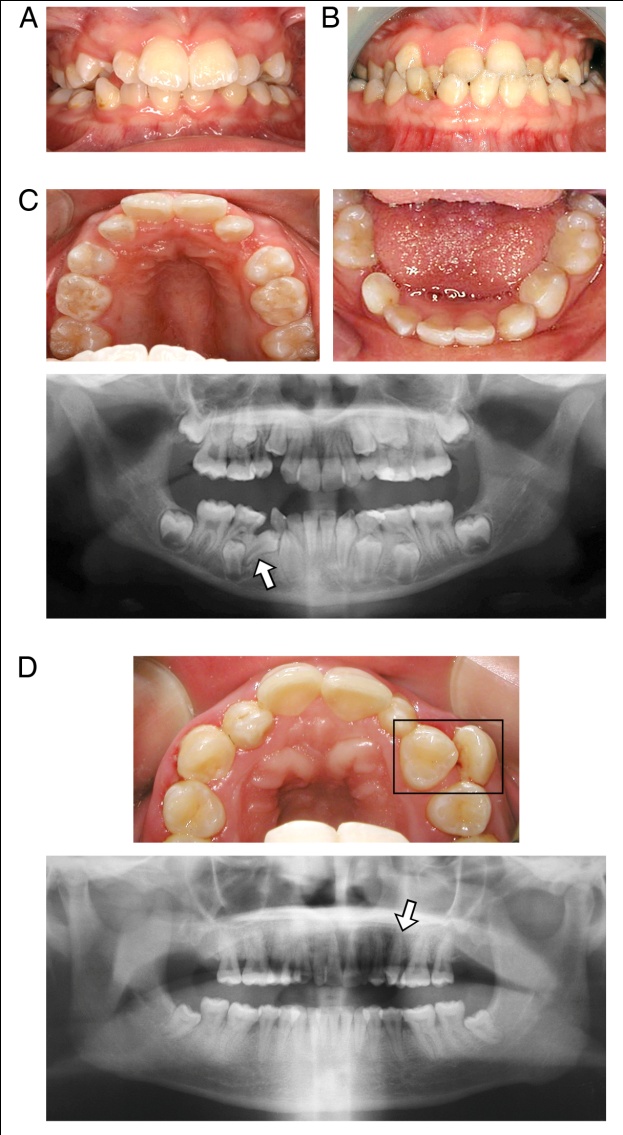

Figure 1 from Modified AltRAMEC treatment of Class III malocclusion in Dental Care For The Patient With Down Syndrome Many people with down syndrome, however, enjoy music and may be comforted by hearing it in the dental office during treatment. Use of the dental hygiene interventions of scaling of teeth and root planing including curetting surrounding tissue, orthodontic and restorative. At higher risk for oral disease, patients with down syndrome require specialized oral care instruction; Incidences of dental decay. Dental Care For The Patient With Down Syndrome.

Figure 5 from Oral Health in Down Syndrome Semantic Scholar Dental Care For The Patient With Down Syndrome This guide provides caregivers with advice on how to find dental care for individuals with down syndrome. At higher risk for oral disease, patients with down syndrome require specialized oral care instruction; Many people with down syndrome, however, enjoy music and may be comforted by hearing it in the dental office during treatment. Providing dental care for patients with down. Dental Care For The Patient With Down Syndrome.